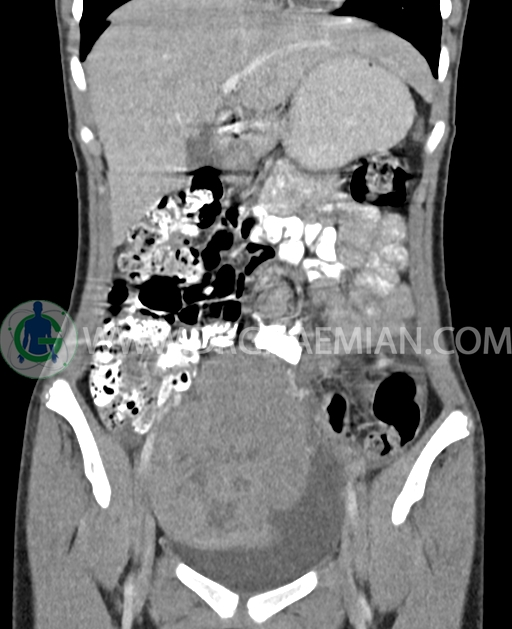

سی تی اسکن شکم و لگن از تشعشعات برای ایجاد تصاویر عرضی مقطعی از نایحه شکم و بین استخوان های لگن استفاده می کند. در این کیس تومور سلول زایا به ابعاد mm 125 x 112 x 80 دیده می شود.

در سی تی اسکن اسپیرال شکم و لگن با کنتراست خوراکی و وریدی (مولتی دیدکتور 16 با مقاطع ظریف و بازسازی های ساژیتال و کرونال) :

توده هیپردنس لوبوله بزرگ به ابعاد 125x112x80mm حاوی نواحی سیستیک داخلی و enhancement قابل توجه پریفرال همراه با آسیت متوسط در فضای شکم و لگن با احتمال بیشتر با منشا از تخمدان راست، درون لگن دیده می شود که در درجه اول مطرح کننده germ cell tumor می باشد .